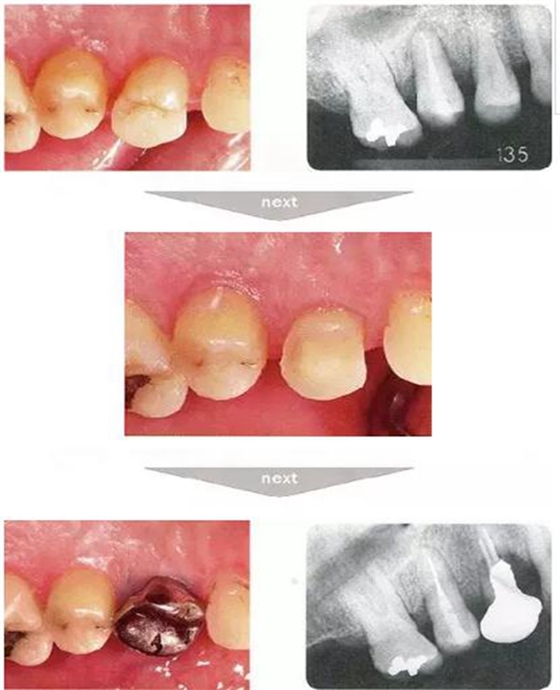

●與外傷相關(guān)的附著喪失①

右下4牙冠牙根破折案例。照片是破折前4個(gè)月拍攝的。牙周袋深度為3mm以下,牙周組織為正常狀態(tài)(右下5是以前由智齒矮小齒移植而來(lái))。破折后,舌側(cè)咬頭破折至傾斜的牙根處,破折片與牙齦相連。

去除破折片進(jìn)行了修復(fù)治療。3年后,上頜腭側(cè)有6mm、近中有4mm的牙周袋。X片可觀察到嚴(yán)重的骨吸收現(xiàn)象??赏茢喑鍪瞧普垡鸬母街鴨适?。

●外傷引起的附著喪失②

右上2修復(fù)物脫落而來(lái)院的患者(上圖是修復(fù)物臨時(shí)裝戴的照片)。頰側(cè)僅有一點(diǎn)有6mm的牙周袋。5個(gè)月前不存在此牙周袋。診斷為無(wú)法保存而進(jìn)行了拔牙。拔牙后,肉眼可清晰觀察到破折線。根據(jù)診查推斷為該深度牙周袋是由于牙根破折導(dǎo)致附著喪失,細(xì)菌沿著破折線進(jìn)入后破壞了牙周膜造成的。